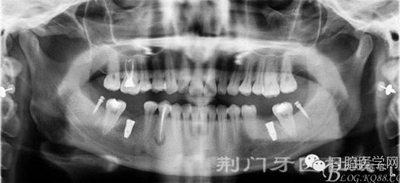

X線片

檢查:16齲壞穿髓,探(-)叩(+++),無(wú)松動(dòng),36 46 缺失,37 47 近中傾斜嚴(yán)重,44畸形中央尖牙體變色,叩(+),溫度測(cè)試無(wú)反應(yīng) ,18 28 38 48 萌出牙體偏頰